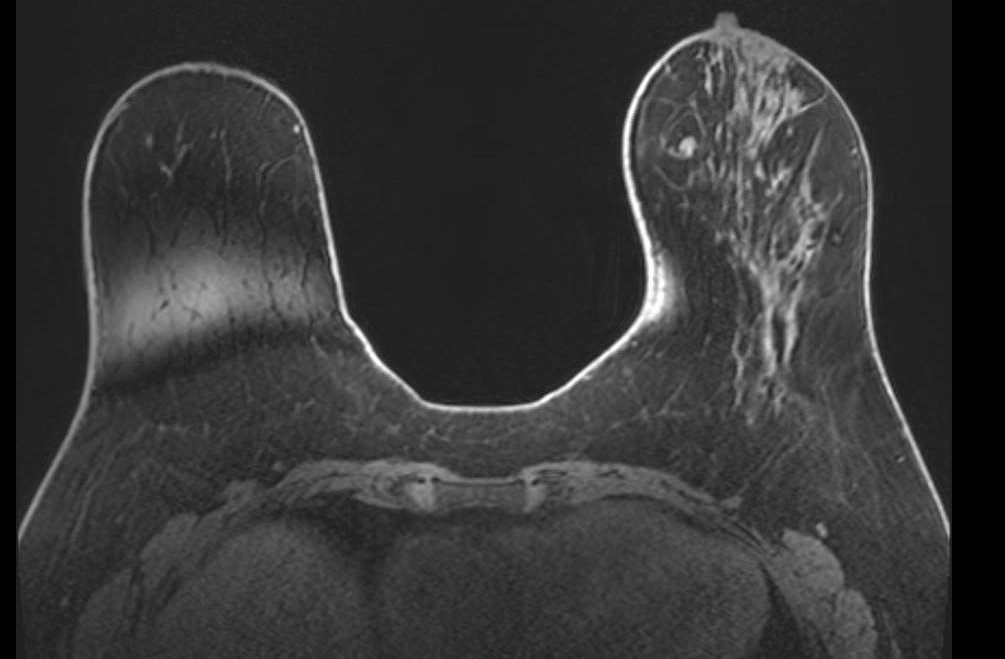

Gibbs Ring Artifact (Truncation Artifact)

Key Points

- Arises from Fourier truncation of finite k-space data

- Appears as parallel ringing bands at high-contrast interfaces (skin-air, skin-parenchyma, implant margins)

- More pronounced in the phase-encode direction

- Most visible on high-contrast sequences such as T2-weighted imaging

- Fix: increase phase-encode steps; zero-fill interpolation

In breast MRI, it is easiest to see at skin-air, skin-parenchyma, and implant margins, especially in the phase-encode direction and on high-contrast sequences (e.g., T2). Reduce it by increasing phase-encode steps (more k-space lines) at scan-time cost; zero-fill interpolation can smooth the appearance but does not recover true spatial resolution. Recognition of the characteristic parallel-band pattern of Gibbs ringing helps differentiate it from true lesions.

Gibbs ring artifact most noticable at implant interface (axial, IR sequence)

Gibbs ringing is a Fourier truncation artifact from finite k-space sampling. Inverse FFT of truncated data fails to represent the highest spatial frequencies at abrupt transitions, generating thin parallel bright/dark bands near high-contrast boundaries.